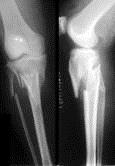

问题 病历摘要: 患者×××,男性,65岁,因车祸致伤左小腿后肿胀、活动受限、疼痛2小时。查体:左小腿上端肿胀,触痛(+),触及在骨擦音,左足伸足母、伸趾功能正常,足背动脉搏动正常。 关于骨不连的X线征,以下叙述哪些是正确的?

选项 A、假关节形成 B、骨质疏松 C、骨痂间无骨小梁形成 D、骨折端硬化,骨折面光滑清晰 E、骨髓腔封闭 F、骨折端有间隙

答案 ABCDEF